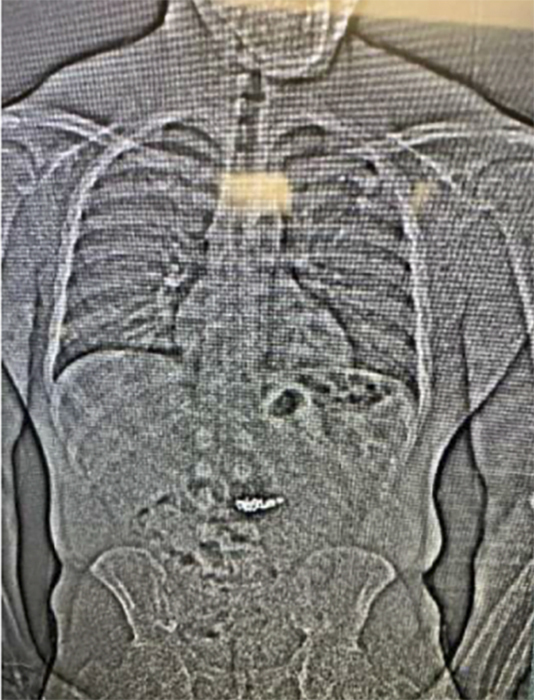

Poliția a cerut o radiografie, care a arătat că în abdomenul său se afla un obiect străin.